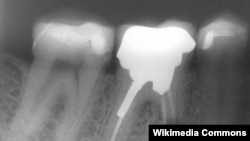

Tuỷ răng (dental pulp) gồm mạch máu nuôi răng và dây thần kinh phụ trách các cảm giác trong răng, nằm trong một khoảng trống nhỏ giữa thân răng gọi là "phòng tuỷ răng" (pulp chamber). Phòng có thể thông ra nhiều ống nhỏ chạy trong trung tâm các rễ của răng, gọi là các kênh phụ (accessory canals), nhỏ như sợi chỉ. Lúc bác sĩ nha khoa lấy tuỷ răng (endodontic therapy, thông thường gọi là "root canal" ), mô mềm, các mạch máu và dây thần kinh trong tuỷ răng bị bỏ đi và bác sĩ dùng nhựa gutta percha để bít kín lỗ hổng còn lại. Chất này lấy hình dạng của phòng tuỷ răng và chụp X quang các ống kênh phụ chứa gutta percha thấy hình giống như sợi dây kim loại.